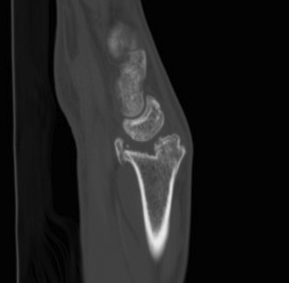

CT

malunionmalunionmalunion